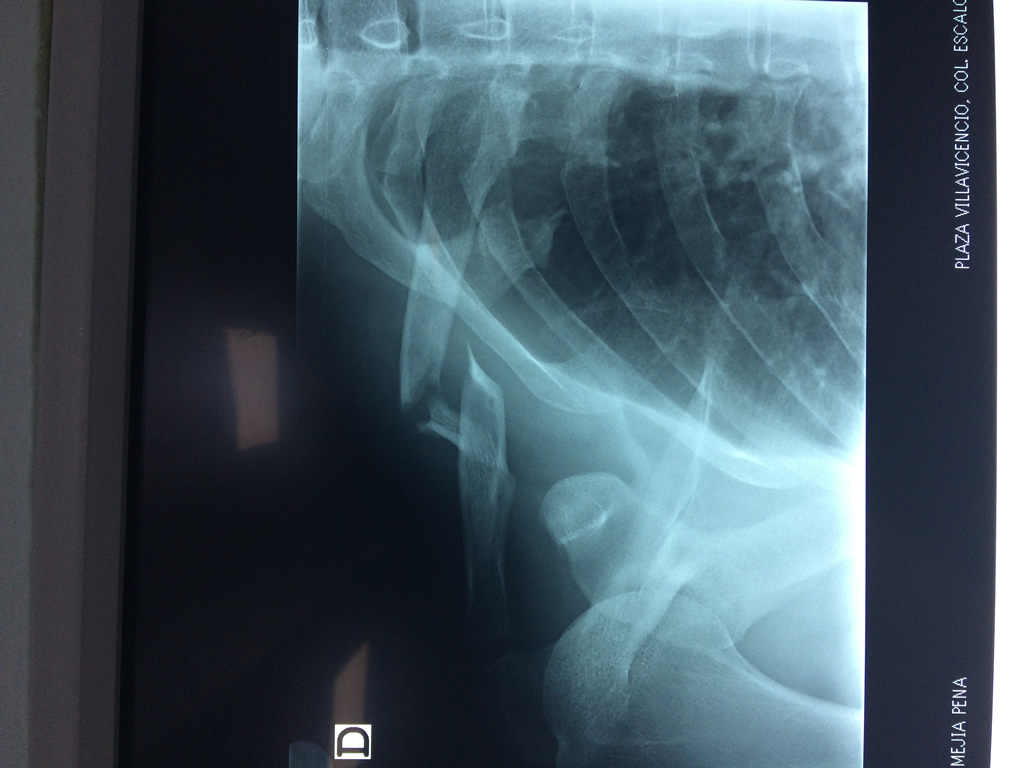

La clavícula es un hueso largo, con forma de "S" itálica, situado en la parte anterosuperior del tórax. Junto con la escápula forman la cintura escapular. Se puede palpar por toda su longitud y se extiende del esternón al acromion de la escápula, siguiendo una dirección oblicua lateral y posterior.